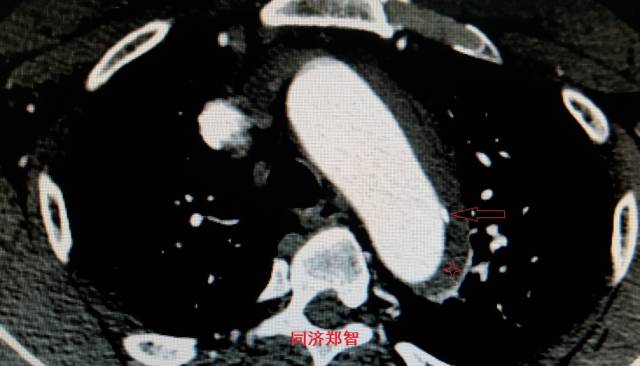

病例九

平扫CT提示降主动脉内膜片征,同时内膜片中可见一钙化点。CTA证实为B型主动脉夹层。